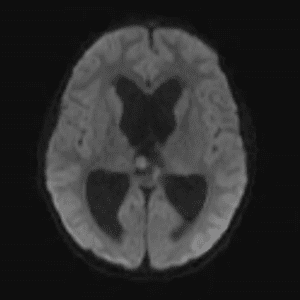

Case #52

Epidermoid cyst